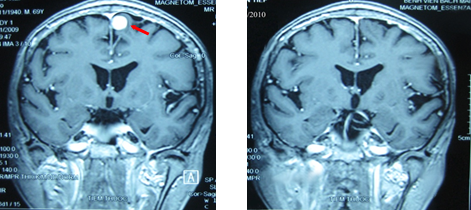

+ Kết quả chụp cộng hưởng từ sọ não: Khối u não vùng đỉnh trái, kích thước 1,7×2,3cm, có phù não xung quanh.